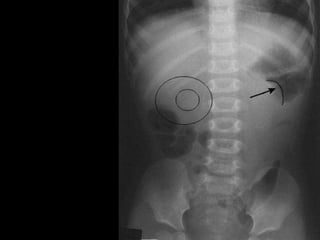

Barium enema

• Coil spring appearance:

• Trapping of barium between the edematous

mucosal folds of the returning limb of

intussusceptum & wall of intussuscepian.

• Meniscus sign:

• Convex intraluminal mass.

The main contraindication of enema is perforation

Coil spring sign

Barium enema •Coil spring appearance: • Trapping of barium between the edematous mucosal folds of the returning limb of intussusceptum & wall of intussuscepian. • Meniscus sign: • Convex intraluminal mass. The main contraindication of enema is perforation

Colo-colic intussusception witha leading point of adenocarcinoma